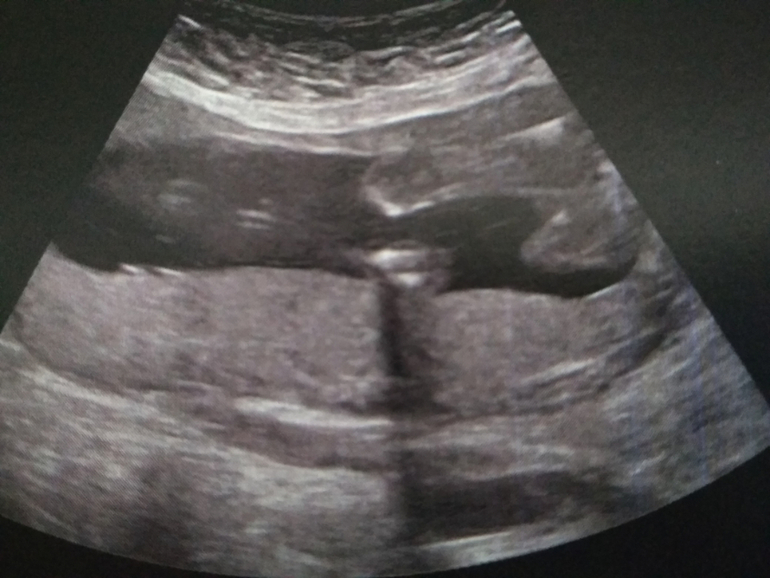

По УЗИ сказали всё ок. Малыш опережает по срокам на пару дней. В подтверждение мальчика приложили мне фото, чтобы я не сомневалась 🤣